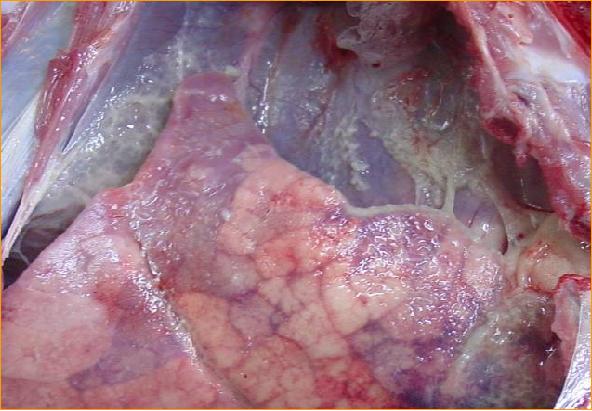

多发性浆膜炎 多发性浆膜炎

多发性浆膜炎